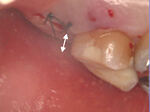

症例6. 再生療法-EPPT-

![]() |

| 右上2番 | 遠心の垂直性骨欠損 |